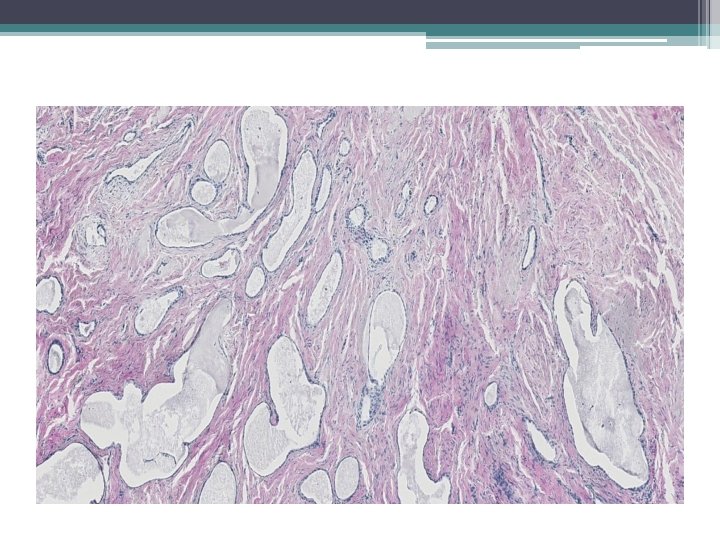

Mikro:

Ektopická prostatická tkáň • • vzácně lokalizace: cervix, vagína věk 21 -65 let mikroskopicky : tubuly a aciny některé papilární, některé kribriformní, s dlaždicovou metaplázií

• Mikroskopicky: • dobře ohraničená hnízda s vrstevnatým dlaždicovým epitelem a tubuly vystlané jednou až dvěma řady kubických buněk, nebo dlaždicovými buňkami. V centru hnízd může byť přítomná nekróza s kalcifikací, nebo keratinové perly.